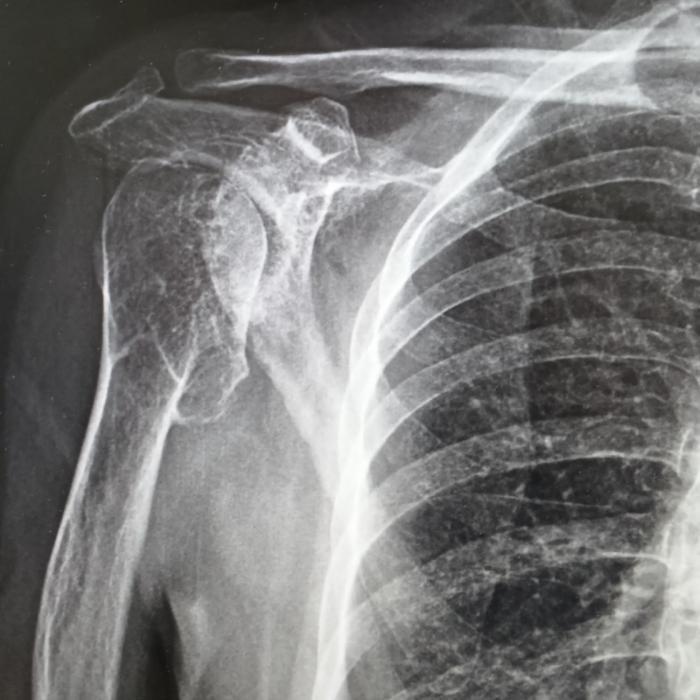

患者右肩疼痛已超过5年,日常梳头、穿衣均受影响。多次接受针灸、外敷药等保守治疗效果不佳。2025年10月MRI检查显示:右肩关节严重退行性变,肱骨头塌陷变形伴多发骨赘,关节腔积液及滑膜炎,同时存在盂唇损伤与肩袖损伤,冈上肌撕裂伴严重退变。

在成都市第三人民医院评估后明确诊断为右肩关节重度骨性关节炎伴肩袖损伤。考虑其关节结构破坏重、功能需求高,团队为其制定反式人工肩关节置换方案。